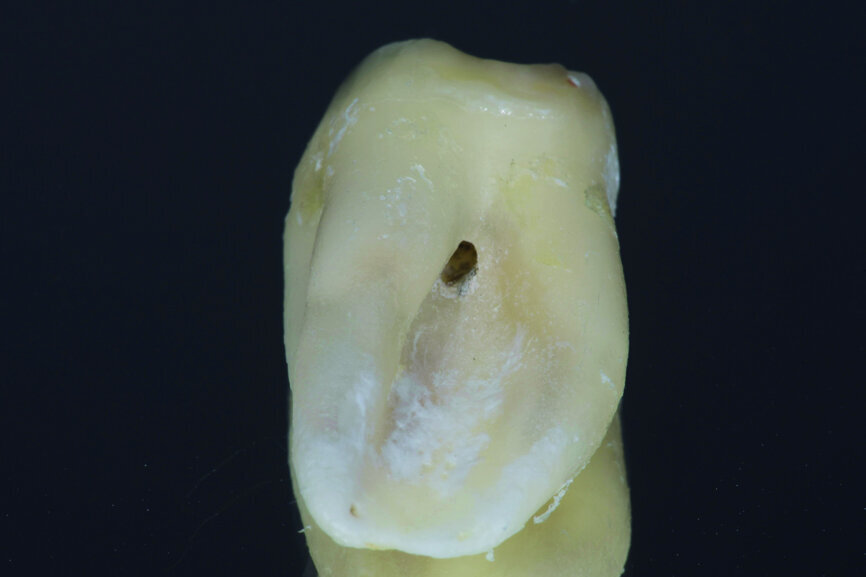

Fig. 12: Pulp chamber floor perforation, immediately after extraction.

Fig. 13: Pulp chamber floor perforation, tooth cleaned.

After local anaesthesia with 2 per cent mepivacaine with 1:100,000 adrenaline, the right maxillary second molar was atraumatically extracted. Initially with a size 15c surgical blade, the periotomy was realised and then the tooth was extracted after separating the roots to avoid unnecessary trauma to the alveolar bone. Then the donor right maxillary third molar was extracted after periotomy as described and transplanted into the adjacent site. Because of the slight differences in the root anatomy, it was necessary to remove the intraradicular bone septum of the receiving site to al- low tooth positioning, and a odontoplastic of the donor tooth crown was performed to maintain it not in occlusion. An antibiotic (amoxicillin/clavulanic acid, 1 g, by mouth twice a day for five days) was prescribed, along with rinses with 0.2 per cent chlorhexidine. The tooth was keep stable with sutures (Fig. 8). A periapical radiograph was taken (Fig. 9). At the suture removal at two weeks, the tooth showed good stability, and positive adaptation of the soft tissue was observed (Fig. 10). At four weeks, the tooth was stable and the soft tissue looked healthy (Fig. 11). The patient did not show any adverse effects and stated that the tooth was fully functional. Examination of the avulsed second molar showed the extent of the perforation (Figs. 12 & 13).